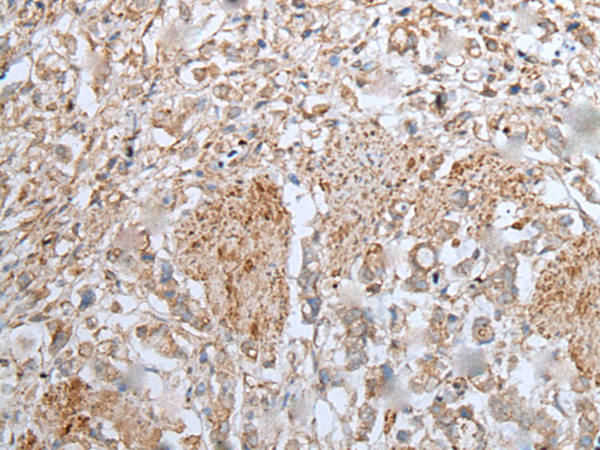

IHC positive control: |

Human cervical cancer and human thyroid cancer |